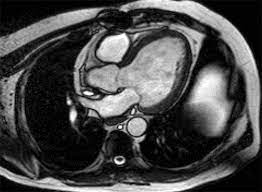

Heart conditions run in Ravi's family, and the fear of the unknown loomed large. His doctor recommended a cardiac MRI, a non-invasive imaging technique that provides detailed pictures of the heart's structure and function. Ravi hesitated at first. The idea of undergoing a sophisticated medical procedure was daunting, but the assurance of clarity and precision was compelling.

The day of the cardiac MRI arrived, and Ravi was filled with a mix of apprehension and hope. As he lay still in the MRI machine, the advanced technology worked silently, capturing high-resolution images of his heart. The experience was surprisingly comfortable, and the process was over before he knew it.

The results of the cardiac MRI brought Ravi a sense of relief that he hadn't felt in months. The detailed images provided a comprehensive view of his heart, allowing for an accurate diagnosis. It turned out that Ravi had a condition that, while serious, was manageable with lifestyle changes and medication. The early detection made possible by the cardiac MRI meant that Ravi could avoid more invasive procedures and focus on preventive care.